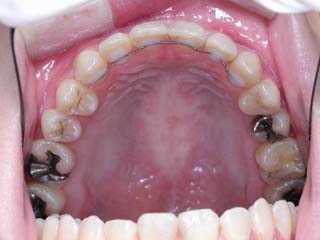

主訴:上の歯が出ている

診断名:顎関節症、上顎前突、叢生を伴う開咬

年齢:20歳

使用した主な装置名:TPB、マルチブラケット装置

抜歯/非抜歯および抜歯部位:抜歯(上顎左右第一小臼歯、下顎左右第二小臼歯)

治療期間:動的処置2年3か月、経過観察3年

費用の目安:保険適応 自己負担金として30~50万

リスク、副作用:外科手術によるリスク、マルチブラケット治療に伴う歯根吸収など偶発症が発生するリスクがある。

比較的強い叢生と、下顎の劣成長を伴う開咬が見られます。成長を終了した永久歯列ですので、骨の大きさのズレへのアプローチは大きく別れる所です。程度が小さければ、歯の傾きで補うように解決しますし、大きなズレであれば、外科的に骨のズレを改善する治療が選択されます。垂直的な問題はその他の不正咬合と比較して、解決が極めて困難な事が多いです。治療後の後戻りが頻繁に見られる不正咬合ですので、外科矯正での改善が望ましい場合も多いでしょう。

術前矯正の仕上げにスプリント治療を行った方が良い場合が多いです。現在、当院での治療では、術前に3か月のスプリント治療を必須にしております。せっかく手術までしてかみ合わせの位置を合わせようとしているのに、顎の関節の位置がずれていたらどうなるでしょう。顎の関節は往々にして顎の大きさのズレをカムフラージュするような偏位を示すので、術後にじわじわと後戻りしているような現れ方で、ズレが見えてくるのでは?このスプリント治療を徹底できたケースでは術後の安定性が極めて高いと感じています。

外科手術は、上顎のインパクションのみをLeFort1にて行いました。